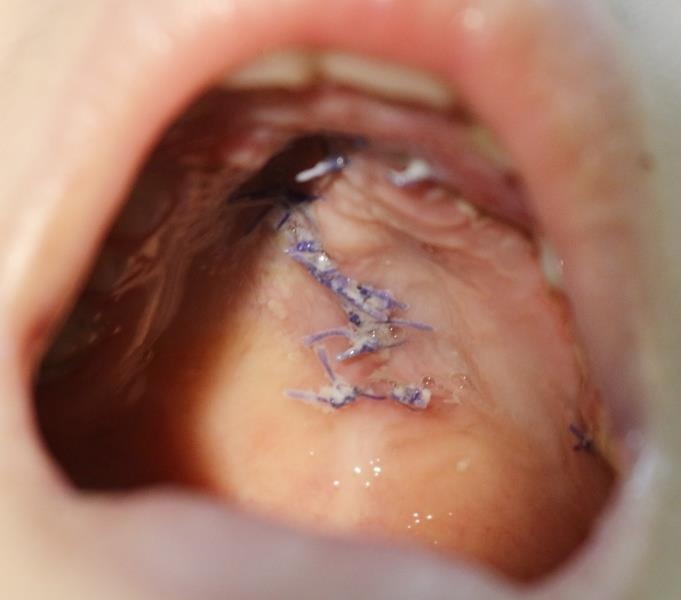

| Hình ảnh vòm họng bị tổn thương được bác sĩ phẫu thuật. Ảnh: Sức Khỏe Đời Sống. |

Sau tai nạn, N. đau và chảy máu miệng, được đưa vào viện. Trẻ nhập viện trong tình trạng tỉnh, chảy máu mũi đã tự cầm, vòm miệng có lỗ thủng nham nhở đường kính khoảng 3 cm còn rỉ máu.

Trẻ đã được xử lý chống nhiễm khuẩn (tiêm uốn ván, kháng sinh cầm máu, giảm đau...). Sau đó, bé được các bác sĩ chuyên khoa Răng - Hàm - Mặt phẫu thuật tạo vạt vòm miệng, đóng lỗ thủng.

Trong quá trình phẫu thuật, các bác sĩ nhận thấy vết thương vòm miệng dập nát, vỡ mất mảnh xương khẩu cái, thông lên nền mũi. Các bác sĩ đã xếp lại xương vỡ, tạo hình vòm miệng cho trẻ. Sau một tuần điều trị, vết mổ tiến triển tốt, bớt nề, trẻ đã được ra viện ngày 17/7.